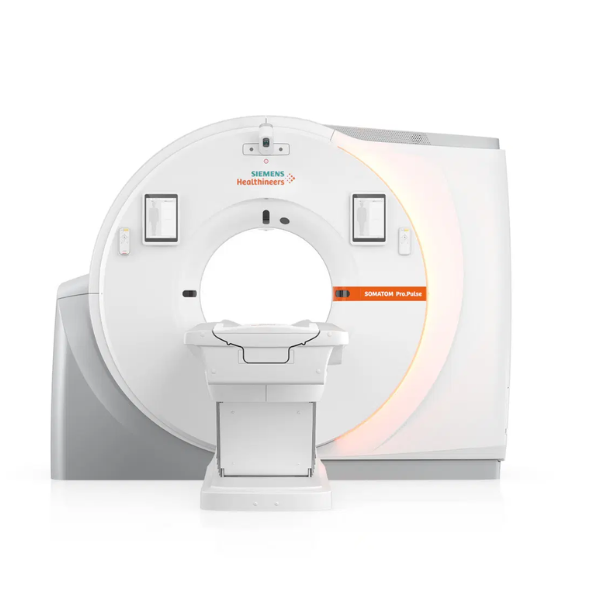

El NAEOTOM Alpha de Siemens Healthineers es el primer tomógrafo computarizado con tecnología de conteo de fotones disponible en Venezuela, marcando un hito en el diagnóstico por imágenes. Gracias a su innovadora Quantum Technology, este sistema redefine la tomografía computarizada al ofrecer mayor resolución, mejor contraste y diagnósticos más precisos, superando las limitaciones de la CT convencional.

En el corazón del sistema se encuentran los detectores QuantaMax, capaces de medir cada fotón individualmente y convertirlo directamente en señal eléctrica. Esto permite eliminar el ruido electrónico, mejorar la relación contraste/ruido y obtener imágenes de alta resolución espectral sin aumentar la dosis de radiación. La combinación con la tecnología Dual Source y el potente tubo Vectron X-ray garantiza un rendimiento excepcional incluso en pacientes con alto índice de masa corporal.

El NAEOTOM Alpha ofrece velocidades de escaneo ultrarrápidas y una resolución temporal nativa de 66 ms, ampliando las posibilidades clínicas en cardiología, oncología, neurología y estudios complejos. Sus flujos de trabajo asistidos por inteligencia artificial optimizan la operación y apoyan la toma de decisiones clínicas.

El NAEOTOM Alpha representa el estándar más avanzado en tomografía computarizada de última generación, llevando la medicina de precisión a un nuevo nivel en Venezuela.